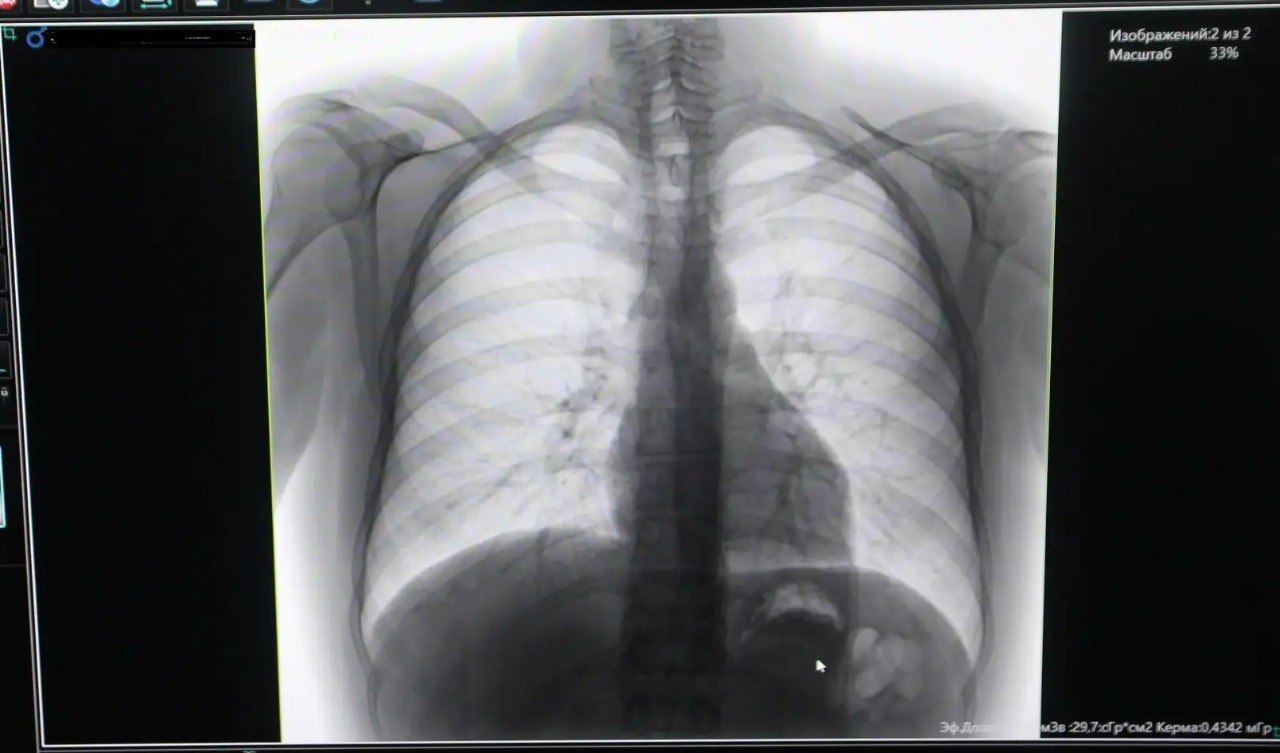

Новый флюорограф позволяет выявлять туберкулез и другие пульмонологические заболевания на самых ранних стадиях, что критически важно для успешного лечения. Как отмечают специалисты, осложнения туберкулеза до сих пор остаются одной из частых причин смерти в мире, поэтому ежегодное прохождение флюорографии рекомендовано всем взрослым.

Главный врач Татьяна Кандаракова подчеркнула: современный цифровой аппарат соответствует всем стандартам и давно ожидался медицинским учреждением. Его внедрение значительно повысит качество диагностики и доступность медицинской помощи для жителей района.